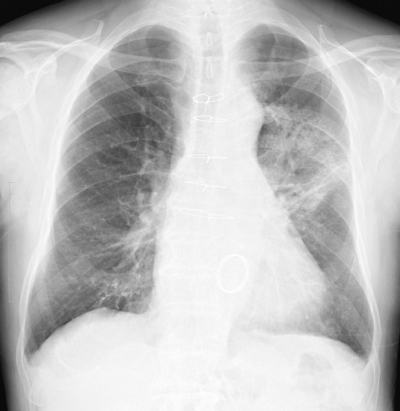

体温 36.4 ℃。脈拍 68/分、整。血圧 122/72 mmHg。呼吸数 18/分。SpO2 97 %(room air)。呼吸音に異常を認めない。血液所見:Hb 10.8 g/dL、白血球 5,400。CRP 0.9 mg/dL。肺癌治療前と今回来院時の胸部エックス線写真及び放射線治療の照射野を示す。

今回来院時